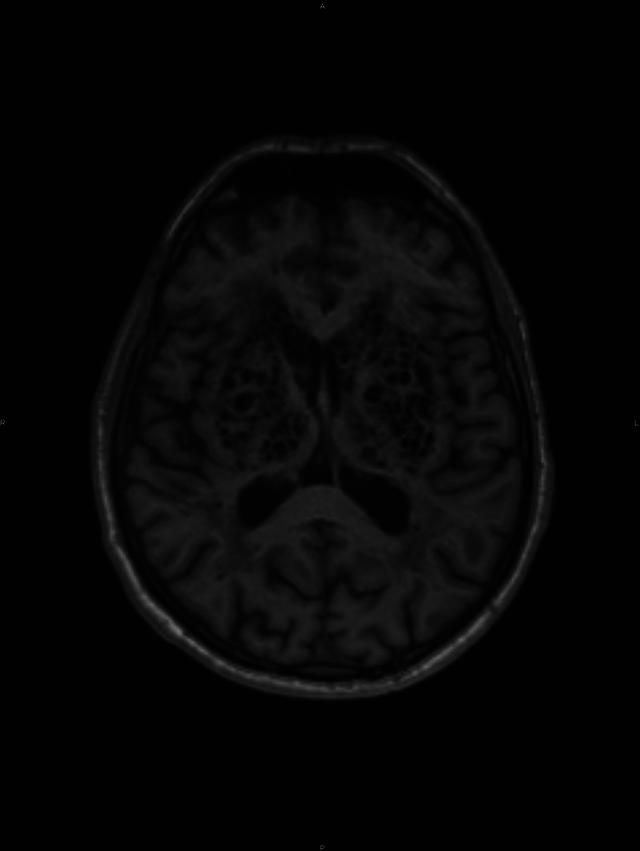

Teaching point: Perivascular spaces, also known as Virchow-Robin spaces, are fluid-filled spaces that surround the vessel walls from the subarachnoid space through the brain parenchyma.

Abstract Image